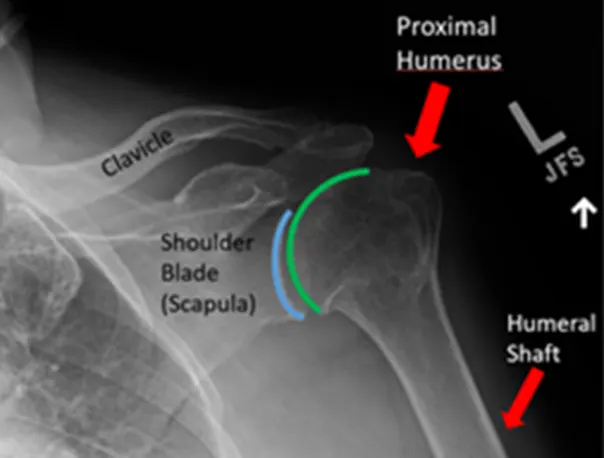

Εικόνα 3: Φυσιολογική ακτινογραφία του ώμου. Η άρθρωση βρίσκεται ανάμεσα στην ωμογλήνη της ωμοπλάτης (μπλε γραμμή) και στην κεφαλή του βραχιονίου (πράσινη γραμμή).